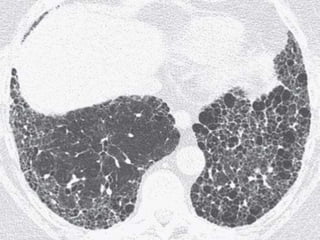

1. Marked fibrosis- On HRCT, IPF is characterized by

intralobular interstitial thickening , results in

reticular pattern in subpleural region - typical

pathological feature of UIP. Dilated and distorted

centrilobular bronchioles are frequently visible

within the areas of reticulation, i.e., traction

bronchiolectasis.

2. Honeycombing- Honeycombing is critical for

making a definitive diagnosis on HRCT,

individual lobules are no longer visible.

Honeycomb cysts usually range from 3 to 10

mm in diameter, but they can be as large as 2.5

cm. The frequency of honeycombing varies

with the severity or stage of the disease.

Findings of honeycombing and fibrosis are

most often symmetric.

3. Patchy involvement- Areas of mild and severe

fibrosis and normal lung are often present in

the same patient, in the same lung, and in the

same lobe.